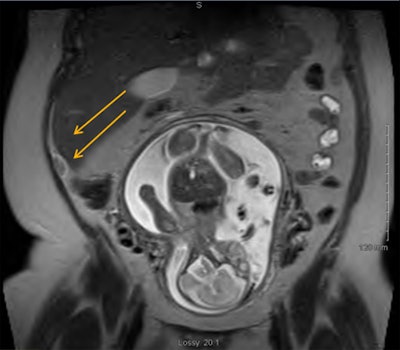

MRI exams were conducted on a 1.5-tesla magnet with a pelvic coil. The imaging protocol included axial, sagittal, and coronal T2-weighted steady-state fast spin-echo (SSFSE) sequences, as well as axial steady-state free precession (SSFP), and axial short-tau inversion-recovery (STIR) sequences. Ultrasound was performed by a certified technologist, with radiologist backup, as needed.

Of the 115 women who were imaged with MRI, the appendix could be seen in 92 (80%) of cases, compared with 23 occasions (20%) when the appendix was not visualized. Among the patients whose appendix could not be seen on MRI, 18 women had no etiology of pain and were treated as if they did not have acute appendicitis. The other five patients with pain were found to have ureteral stones, transverse colitis, inguinal hernia, and calyceal ruptures in two cases.

Acute appendicitis was diagnosed in 21 patients (23%), of which 19 cases were proved by pathology. Also, one woman had a neuroendocrine tumor, and one person had mural endometriosis.